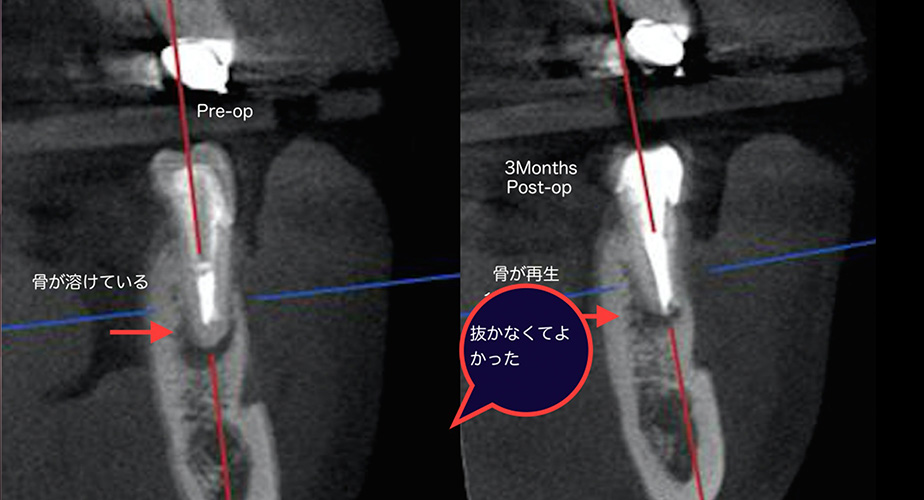

前医から「歯が割れているかもしれない」と診断され抜歯を勧められた。

| 主訴 | 前医から「歯が割れているかもしれない」と診断され抜歯を勧められた。 |

|---|---|

| 治療期間 | 根管治療1時間2回。3か月後CT撮影し治癒を確認後、クラウン修復。 |

| 治療内容 | マイクロスコープとCTを使用した根管治療3か月後に治癒を確認してクラウン修復を行った。 |

| 治療費 | 根管治療:¥121,000円 土台:¥22,000円 仮歯:¥11,000円 クラウン修復:¥154,000円 |

| 治療の リスク |

特になし |